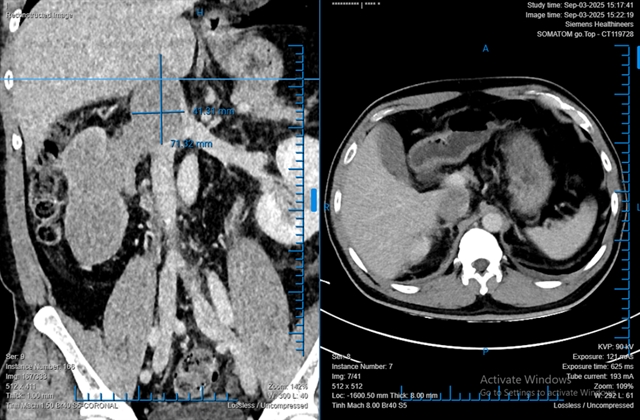

Doctors at Bình Dân Hospital in HCM City have successfully performed a fully robotic radical nephrectomy to remove a large kidney tumour, with a...